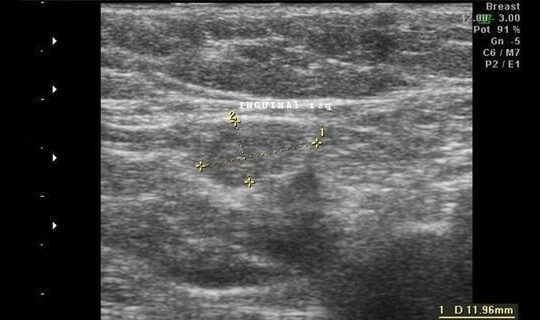

La ecografía es muy útil en la visualización de hernias debido a su capacidad para proporcionar imágenes en tiempo real. En una ecografía abdominal, por ejemplo, es posible identificar una hernia mediante la visualización de una protrusión o abultamiento de tejido en el área afectada. Además, la ecografía también permite evaluar el tamaño y la ubicación de la hernia, así como examinar los tejidos circundantes para detectar cualquier complicación o problema adicional.

En el caso de las hernias inguinales, la ecografía puede proporcionar una visión clara de la hernia y de la herniación de tejido a través de los músculos de la ingle. Esto permite a los médicos determinar el grado de compromiso de los tejidos y tomar decisiones informadas sobre el tratamiento.